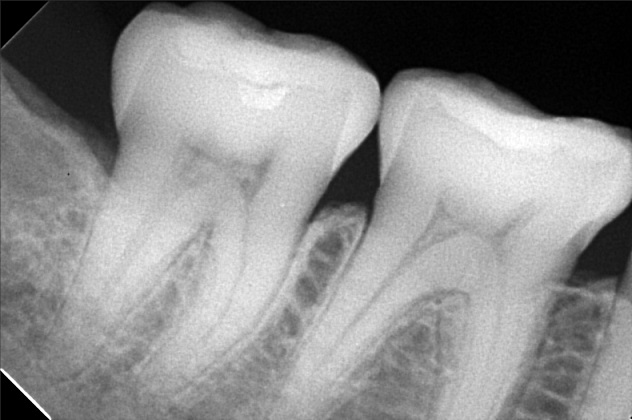

Edit Record Check our patient data records. Add patient information Patient Info Profile picture Last Name First Name Middle Name Birthdate Age Street Barangay City Country Zip Code Contact number Email Procedure 4/8/22- check up ***pano/ ceph ***#46 exo presence of lip tie 04/02/22 odontectomy 48/38- class 3/ mesioverted exo 46/ tongue tie/ ankyglossia frenectomy (laser) pt under IV CS Ozone therapy ****ff up after 2 weeks/ ***for orthodontic treatment 06/16/22 LC 24 OD/ CAOH LC 47 M op/ OZONE 1/11/23- Adj , 16niti Upper, Rotational Wedge # 42D , reattached #35 11/04/22-OP/LC 15,36,26,/mta/XRAY 11/16/22-InsOfBraces/Niti 14/14(MBT0.22) 12/07/22-adj 01/11/23- adj 04/12/23- same wire U/ Lower NiTi 16/ reattached #34,15/IPR between #32-33 05/05/23- U same wire; L SS-16; Resto #14DO, #15MOD, #16D 06/07/23- Informed Consent Resto #14DO (redo) Ortho UL same wire Remove RW #33 Monkey elastics #13-#23-#33-#43 07/19/23- Lc 36 occusal, lingual 18 ss U 18ss l rw 33 distal 08/18/23- 09/15/23- same wire #22 extrude 10/13/23 - adjustment, same wire - RW on #12 mesial 12/13/23-16X16 L -Penguin Cross Elastic -Upper to Right -Lower to left 01/12/24- adjustment same wires X-elastics on posterior Pms FOR removal on APRIL 02/21/24 same wire chain upper and lower rabbit to 3's to 4's 03/22/24 same wire rabbit 43 to 25 chipmunk 13 to 45 RW #45 distal 04/19/24 Removal of braces for retainers( vacuumed retainers) OP w/ flouride impression U/L 07/19/25 op with air polisher 03/18/26 Summer smile promo LC #14 - M,O, D + caoH + GI #15 - M,O,D + desen #16- M, O, Li + caoH + GI 03/26/26 Redo 04/08/26 check up 05/14/26 LC #16- fiber + mta File dana46.jpg File 2 file_0001_1_2.jpg File 3 file_0001_3.jpg File 4 dana_aguto.jpg File 5 dana_aguto_02.jpg File 6 dana_aguto_03.jpg File 7 dana_guto_04.jpg File 8 img_20240406_103512.jpg File 9 File 10 File 11 File 12 File 13 File 14 File 15 File 16 File 17 File 18 File 19 File 20 Retain Record Retain Record Yes No Save Your Changes